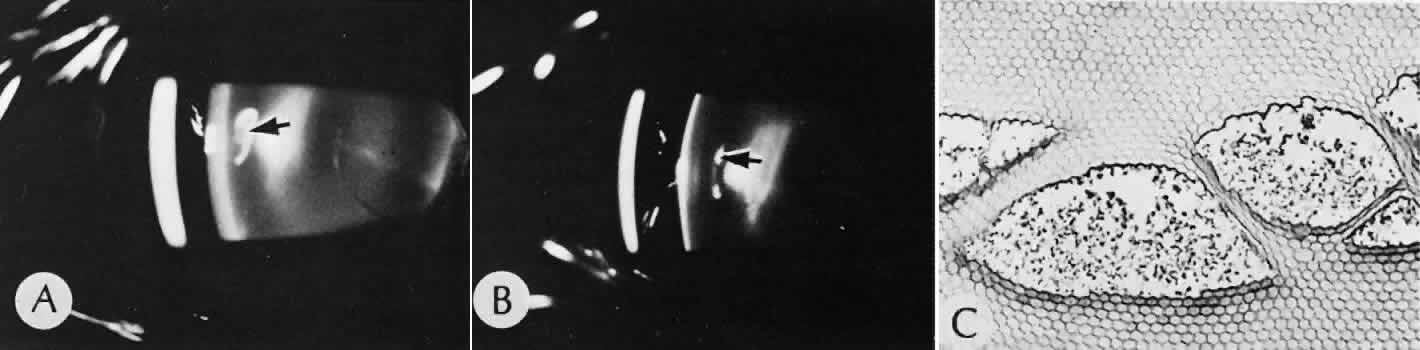

A flat anterior chamber is characterized by anterior displacement of the iris to near or in actual contact with the posterior surface of the cornea. The most common cause is leakage of aqueous along one of the suture tracks. Prolonged decompression of the anterior chamber increases the risk of synechiae formation and intractable secondary closed-angle glaucoma. Corneal endothelial damage may result in bullous keratopathy. Choroidal edema (choroidal hydrops or detachment) (Fig. 31) may be associated with a flat anterior chamber and may potentiate the condition. The choroidal edema will slow or stop aqueous production by the ciliary body, further delaying reformation of the anterior chamber. The histologic characteristics of choroidal edema consist of spreading of the choroidal tissue in a fanlike configuration and eosinophilic fluid filling the intervening spaces. The edema fluid may be lost in processing, leaving multiple apparently empty spaces.

Fig. 31. A case of choroidal detachment. A. By fundus reflex, a large dome-shaped mass can be seen originating from the choroid. The differential diagnosis would include uveal malignant melanoma. In this case, the clinical findings were due to choroidal detachment from the sclera because of fluid accumulating in the suprachoroidal space following cataract surgery. B. The histologic section from another case of choroidal detachment illustrates the location (arrow) and extent of the detachment. In this case the detachment extends to the region of the ciliary body limited anteriorly by the attachment of the choroid to the scleral spur. The displacement of the ciliary body will result in apparent shallowing of the anterior chamber. (Hematoxylin-eosin stain; × 6.)